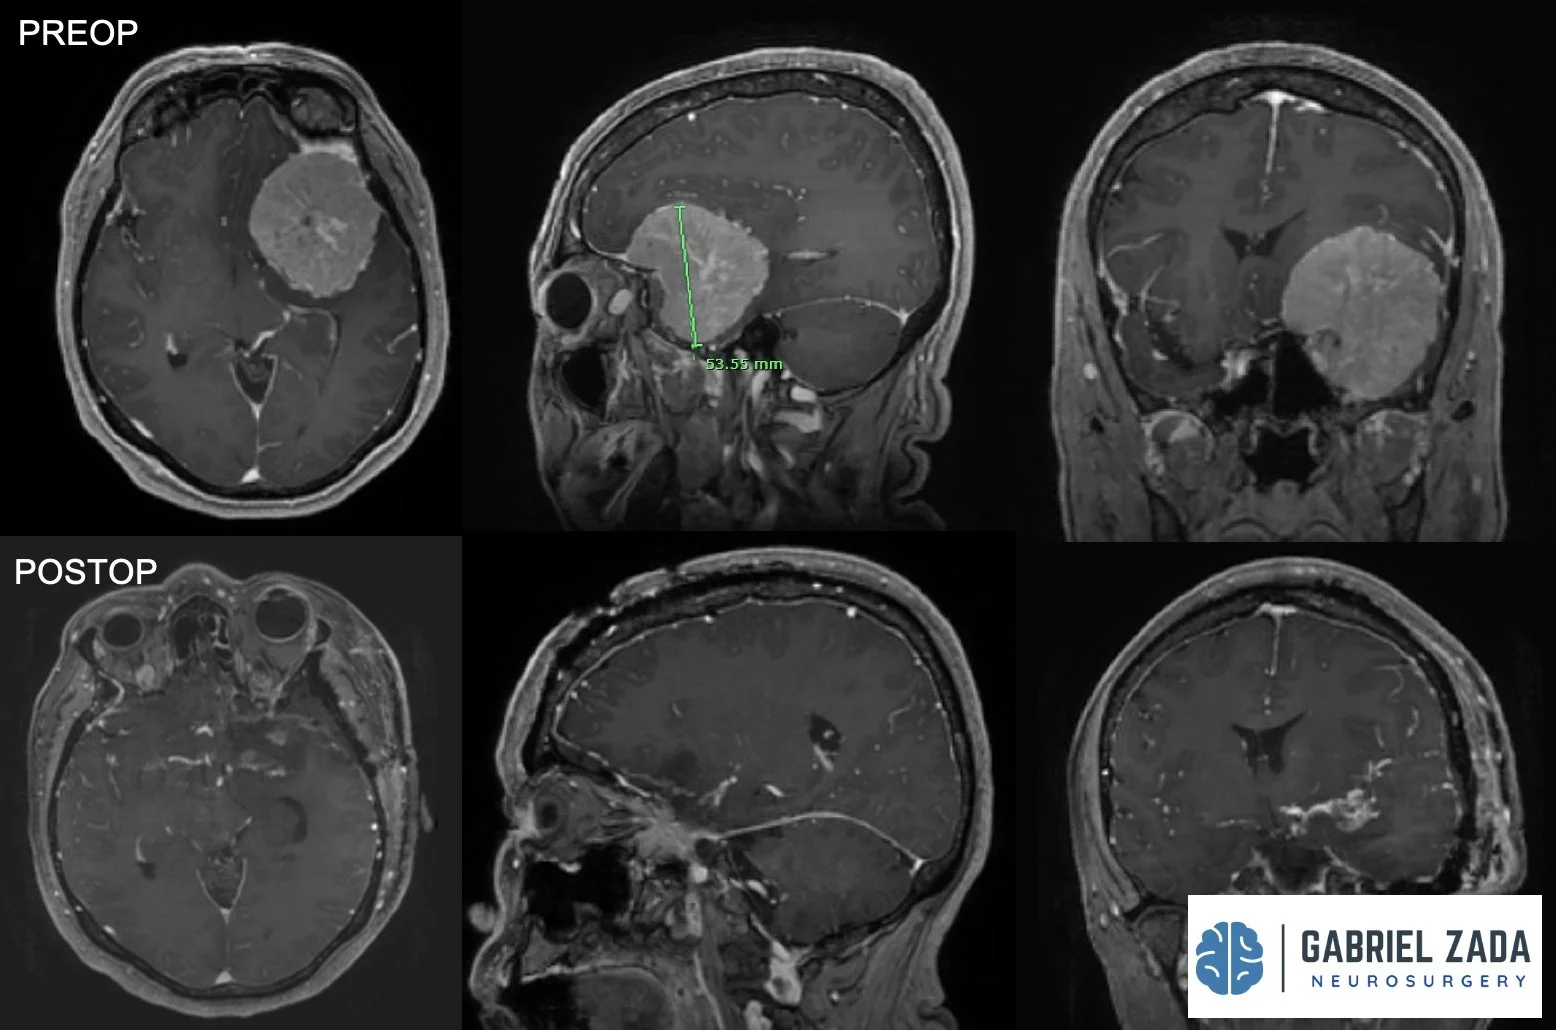

Explore this comprehensive gallery featuring pre‑ and post‑operative imaging of patients with skull‑base tumors treated by Gabriel Zada, MD, MS, FAANS, FACS. These cases highlight Dr. Zada’s expertise in advanced neurosurgical techniques and outcomes.

*Representative cases shown for educational purposes. All images de-identified. Individual results vary.